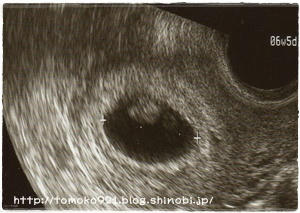

エコーを見ると。。。

20090914_2.jpg

大きくなってる~!!

左が頭、右がおしり。

よく見ると、手足をバタバタさせてるのが分かった(*´∀`*)

現在、身長約2cm!

2cmなのに手足をバタバタ!!笑

人間ってすごいねぇ~